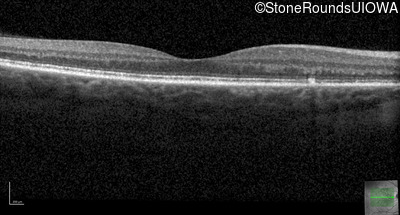

Optical Coherence Tomography - Right - 20/20 -1

Exemplar / OCT Stack

OCT Stack